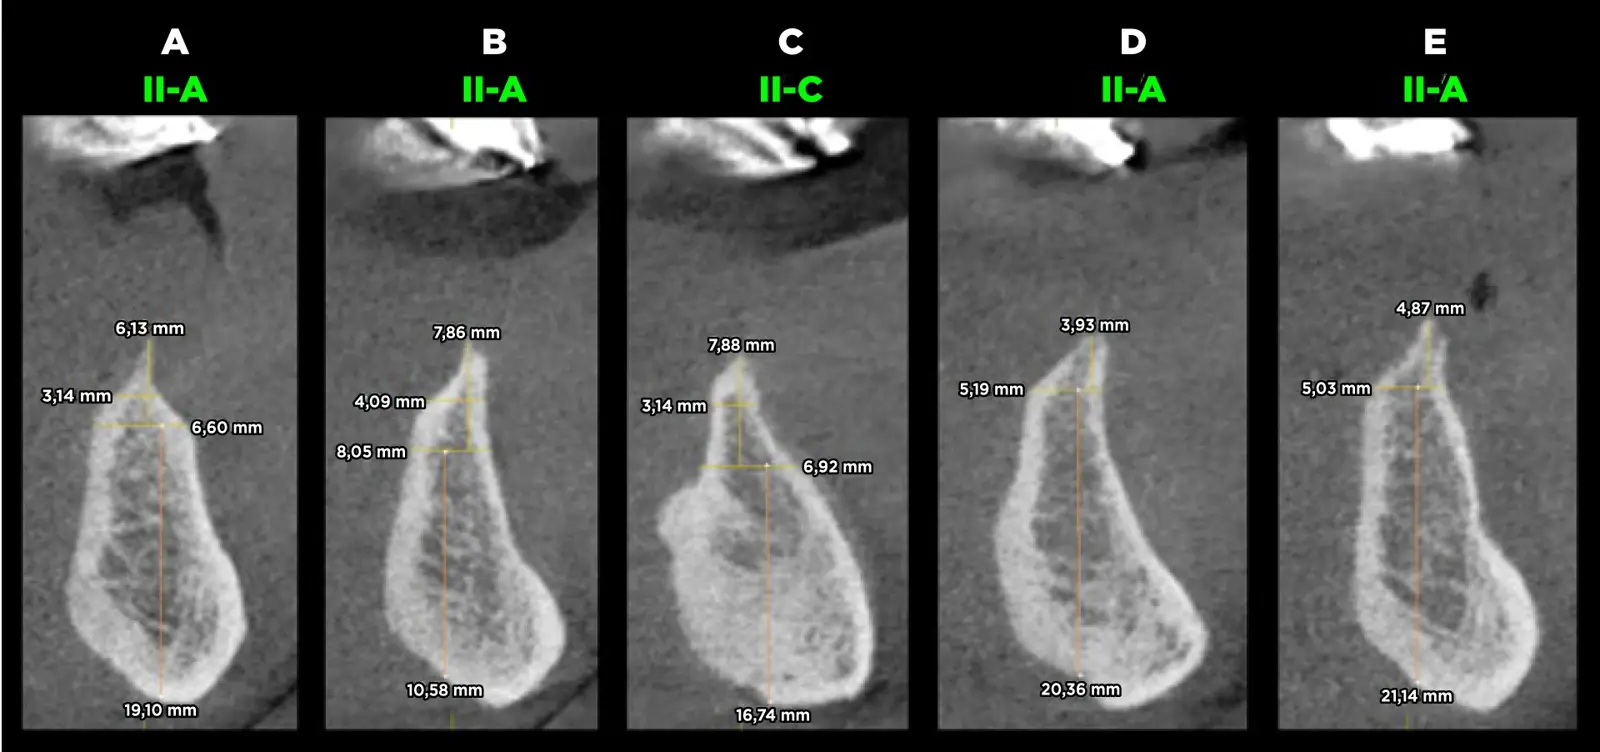

Se procedió con la confección de la placa base y los rodetes de cera previa estabilización oclusal mediante un encerado de diagnóstico y planificación. Se confeccionó la guía quirúrgica bien adaptada y en oclusión para corroborar la ubicación tridimensional de los implantes. El paciente acudió a la consulta con una tomografía computarizada volumétrica previa a la confección de la prótesis inferior, en donde se realizaron los cortes tomográficos teniendo en cuenta los reparos anatómicos. Se evaluó la calidad ósea y se planificó la colocación de cinco implantes en posiciones A, B, C, D y E, con la eliminación previa de estructura ósea debido al escaso ancho que ésta presentó y que dificultaría la preparación e instalación de los implantes (Figura 3).

Evaluación de la calidad ósea

Figura 3. Evaluación de la calidad ósea del paciente según la clasificación de Lenkholm y Zarb modificada por Rosas y cols. donde se observa el hueso tipo II-A y II-C en el paciente.

La calidad ósea es una de las variables más importantes que influye de manera directa en la estabilidad de los ID y es importante medir el grado de trabamiento de los implantes dentales en cada tipo de hueso. En 2022, Rosas y cols.5-7 presentan una modificación de la clasificación de calidad ósea de Lekholm y Zarb donde se considera la microestructura del patrón trabecular, el tamaño de los espacios medulares, los huesos regenerados y los huesos con patología:

Hueso Tipo I: hueso predominantemente cortical que rodea al hueso esponjoso de escasa cantidad con trabéculas nítidas y visibles en toda la imagen y presencia de espacios medulares pequeños y visibles8-10.

Hueso Tipo II: se subdivide en tres tipos:

Hueso Tipo II-A: hueso cortical grueso que rodea al hueso esponjoso de cantidad abundante con trabéculas nítidas en toda la imagen y presencia de espacios medulares pequeños y visibles5-10.

Hueso Tipo II-B: hueso cortical grueso que rodea al hueso esponjoso de cantidad abundante con predominio de trabéculas difusas en el hueso medio y basal y presencia predominante de espacios medulares amplios y visibles. Esta calidad ósea es de alto riesgo por ser literalmente un hueco5-10.

Hueso Tipo II-C: hueso cortical grueso que rodea al hueso esponjoso de cantidad abundante con predominio de trabéculas muy gruesas y nítidas en la basal, con presencia de espacios medulares pequeños y visibles. El tercio superior es parecido al II-B5-10.